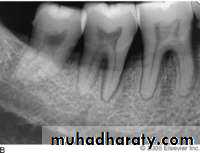

(A) Improper vertical angulation (excessive) obliterates viewing this proximal surface carious lesion. (B) Proper vertical angulation shows interproximal cariesDental Caries

Radiograph of occlusal caries. This radiograph shows (1) severe occlusal caries, which appears as a large radiolucent lesion in the first molar

Radiograph of buccal or lingual caries. Buccal or lingual caries on this mandibular second premolar appears as a round radiolucency (superimposed over the pulp chamber)

Radiograph of cemental (root) caries. The large radiolucency on the distal surface of the distal root of the first mandibular molar

Radiograph of recurrent caries. This radiograph shows (1) radiolucent caries under the metallic restoration